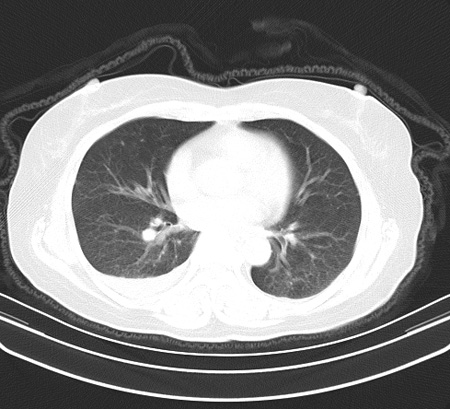

以下是引用余辉在2009-2-19 20:10:00的发言:[br]多考虑急性感染性病变,右中叶尚可见多枚小斑片状影,多为化脓性肺炎,双侧胸腔积液

以下是引用随光逐影在2009-2-19 20:33:00的发言:[br]1)考虑右肺炎症;建议抗炎治疗后复查。2)双侧胸腔积液(以右侧为甚)。

以下是引用花凤凰在2009-2-19 20:46:00的发言:[br]病人有发热,胸痛急性起病,主要病变位于右肺中叶外侧段,呈楔行改变,位于外带胸膜下,考虑为肺梗塞可能!!!!!!!!!!!!!!!!!!!!!!!!!!!!!!!!!!!